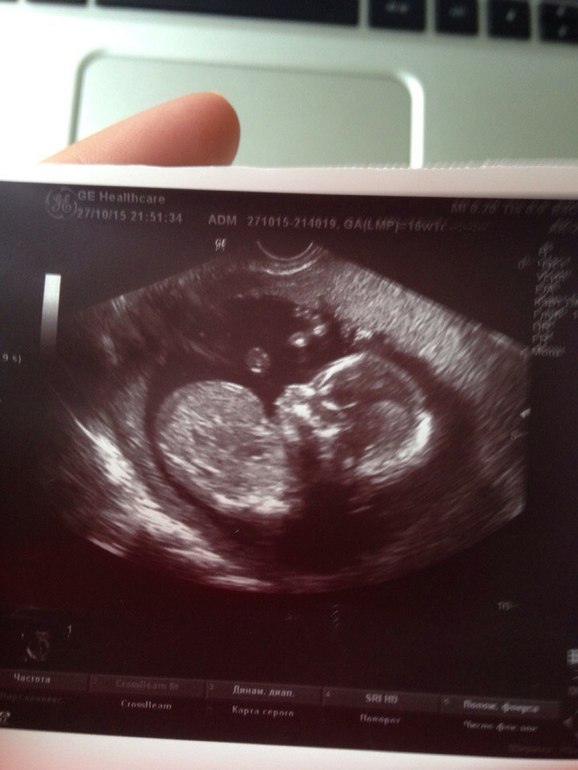

И узииии, самое интересное) ходили с мужем) срок у нас 16-17 недель. любимый думал видимо, что ему сейчас на экране червячка покажут непонятного и все. Но когда начали показывать по телевизору настоящего человека с головой, руками-ногами, пальцам и сердечком он начал нервно хихикать и подхрюкивать

У нас все хорошо, развиваемся-растем) плацента отличная, шейка на месте)

И у нас будет девчонка! (если ничего не отрастет, но доктор сказала, что прям почти 100%))) Муж рад, он дочку и хотел, а я в принципе рада, что все отлично)

А вам салют ногой от нашей девочки